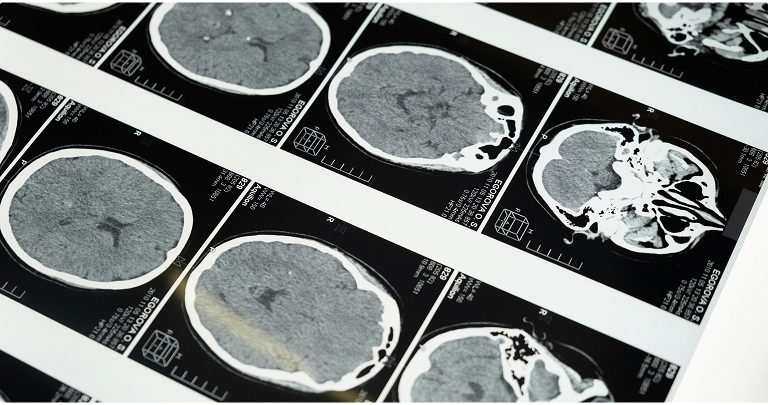

Certain pathological changes are found in the brains of people with Parkinson’s, including so-called Lewy bodies. These are abnormal inclusions found inside some neurons and contain aggregates of misfolded alpha-synuclein, along with other cellular components. Lewy pathology is a key neuropathological hallmark of Parkinson’s. The exact mechanisms by which alpha-synuclein aggregation contributes to neuronal dysfunction and cell loss, and how this relates to clinical symptoms, remain an active area of research.

The main motor symptoms of Parkinson’s include tremor (shaking), rigidity (muscle stiffness), bradykinesia (slowness of movement), and postural instability (loss of balance), which often becomes more prominent later in the disease. These symptoms are linked to degeneration of dopamine-producing neurons in the substantia nigra, leading to reduced dopamine levels in the striatum and disruption of basal ganglia circuits that normally help initiate and smooth movements. This imbalance contributes to the characteristic motor features of Parkinson’s.

- Deep brain stimulation (DBS): For patients who no longer respond to medications and who suffer from motor fluctuations, deep brain stimulation (DBS) may be an option. It involves implanting electrodes in specific areas of the brain that control movement in order to alleviate motor symptoms.